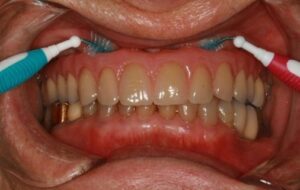

10) Instrumentation : détartrage supra gingival et polissage des cols implantaires, thérapie laser photochimique ou photodynamique selon l’aspect inflammatoire ou infectieux des tissus (fig. 11 à 13).

Figure 13: Vérification de l’espace disponible et de l’aptitude du patient à passer des brossettes